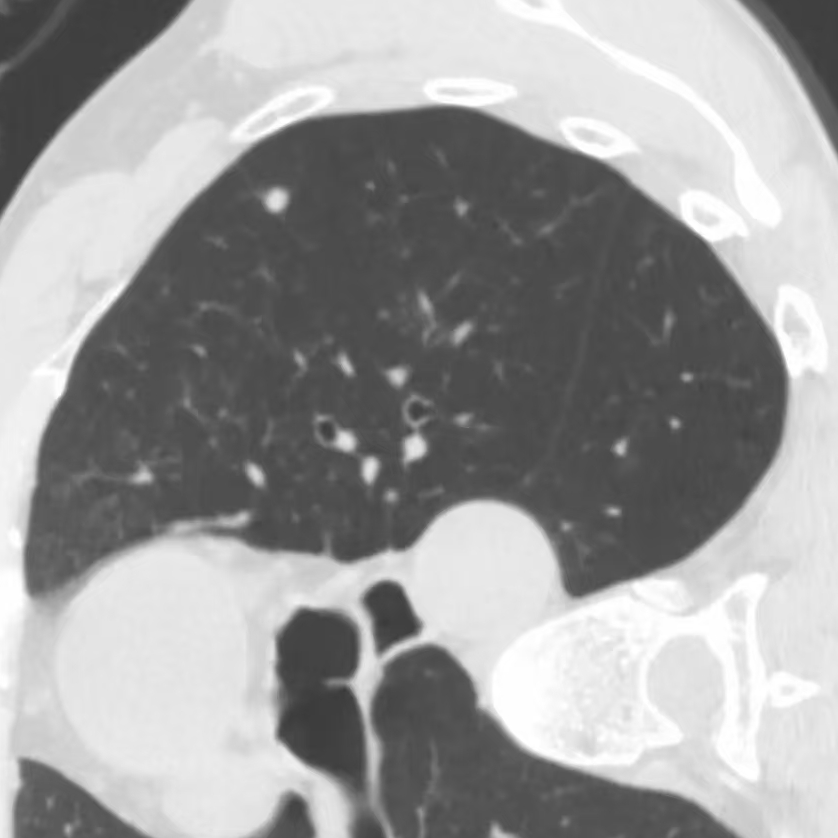

健康直通车: 健康是生命的宝贵财富,也是幸福生活的基石。为了更好地服务广大百姓,传播健康知识,葫芦岛市第二人民医院推出“健康直通车”专题栏目,将专业的医学知识以通俗易懂的方式传递给每一位市民,掌握科学的疾病预防方法,共同构筑健康中国的坚实基石。 什么是肺结节 肺结节是指肺内直径小于或等于3cm的类圆形或不规则形病灶,影像学表现为密度增高的阴影。大于3cm的称肿块。肺结节依其密度不同可分为实性结节、部分实性结节、磨玻璃结节,其中部分实性结节的恶性可能性最大,磨玻璃结节次之,实性结节尤其是小的实性结节结节最可能是良性的。 肺结节的常见病因 1、良性(约90%) 🔸 感染:结核、真菌、细菌性肺炎后遗留的瘢痕; 🔸 非感染:错构瘤(良性肿瘤)、炎性假瘤、血管瘤等。 2、恶性(约10%) 🔸原发性肺癌(如腺癌、鳞癌); 🔸转移性肿瘤(其他器官癌症转移至肺)。 如何根据影像判断肺结节性质 1、依据结节大小判断 🔸小于0.5cm的肺结节绝大多数都是良性的,属于微小结节。即使部分小于0.5cm肺结节是恶性的,但是适当的观察不影响预后。每年复查一次胸部CT就可以。 🔸大于0.5cm持续存在的纯磨玻璃结节,观察6个月,若持续存在,不管有无进展均多数是恶性的,视患者意愿,手术可以立即做也可观察至进展再做,不影响预后。 🔸大于0.8cm的部分实性结节恶性可能性非常大,应积极评估结节边缘毛刺、分叶、胸膜凹陷等征象。 🔸若实性部分大于0.5cm,恶性率显著提高。若在3~6个月随访期间实性部分增大或者总体部分增大,都可以考虑手术切除。而即使小于0.8cm的部分实性结节也需3个月就复查对比。 2、依据肺结节形态 如CT上提示病灶形态不规则、毛刺、分叶、胸膜凹陷、空泡征、血管集束征等,符合恶性肿瘤的征象。 🔸结节与正常肺组织之间界限非常清楚的恶性可能性大。 🔸结节密度不均呈混杂密度或均匀较大纯磨玻璃结节也基本是恶性的。 🔸有胸膜牵拉(不管是肺表面的脏层胸膜还是叶间裂部位的胸膜)的恶性可能性大。 🔸结节有浅分叶、细毛刺,密度较高而与周围肺组织边界不清的恶性可能性大。 🔸磨玻璃或混合磨玻璃结节存在小空洞的恶性可能性大。 🔸影像上似慢性炎表现,而没有炎症相关的其他异常,特别当所谓炎症区域内部或一侧与正常肺组织之间界限非常清楚的基本上是恶性的。 3、从结节发展情况来看 所有随访中增大进展的都需要考虑恶性可能,不进展而持续存在的纯磨玻璃结节也需考虑恶性。 葫芦岛市第二人民医院肺结节诊治中心孙振教授深耕肺结节领域四十余载,凭借对临床实践的执着钻研与深厚积淀,在肺结节精准诊断及鉴别诊断领域形成独到见解。他系统总结海量临床病例,创新性提炼出一套科学化、规范化的肺结节全周期诊疗体系,尤其在早期微小结节的影像特征识别、良恶性风险分层等方面积累了丰富经验,为众多患者提供了精准、高效的诊疗方案。 人民医院·人民名医 孙振 主任医师 三级教授 ·葫芦岛市第二人民医院胸外科主任、肺结节诊治中心主任 ·中国医科大学客座教授 ·原央企总医院著名胸外科专家 ·辽宁省医学会胸外科委员 ·辽宁省抗癌协会肺癌专业委员会委员 ·辽宁省细胞生物学学会食管癌专业委员会理事 ·主持多项科研成果获科技成果奖、科技进步奖、国家专科奖项 医学成就 从事胸外科临床工作近40年,担任胸外科首席专家及科室主任20余年,是我省胸外科领军人物,推动肺癌、食管癌等胸部肿瘤外科的规范化诊疗,在央企总医院牵头成立了肺结节诊疗中心,率先开展CT引导下肺内小结节定位切除,既确切完整切除肺内小结节,又降低肺功能损害。 专业特色 擅长肺癌、食管癌的外科手术和综合治疗,在各类高难度胸外伤手术治疗、胸腔镜微创手术、胸腺瘤手术及复杂并发症处理方面具有高深造诣,尤其擅长肺癌早期诊断,胸部小结节CT早期肺癌的鉴别等。完成各类高难度胸外科手术5000余例,其中微创手术占比达90%,治愈率达98%,多项业务填补省内空白。 开展的高难手术 胸腔镜肺部结节微创手术、肺癌根治术、食管癌根治术、各种纵隔肿瘤切除术、胸骨后甲状腺手术及胸部复合性外伤的抢救手术等。